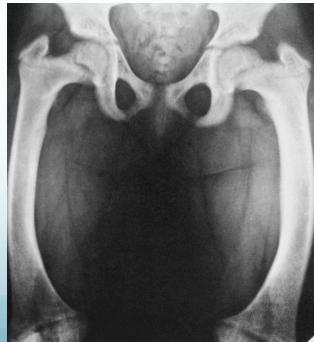

- Widened physis (epiphyseal growth plate)

- Cupping of metaphyseal end (weak new bone)

- Irregular metaphyseal end

- Osteopenia (decreased bone density)

- Thin cortex

- Deformity

Lower Limb Deformities

- Bowing of legs: most common presentation

- Localized – distal tibiae most affected

- Widened physis (first and most prominent finding)

- Metaphyseal changes:

- Cupping (due to weak new bone)

- Irregular margins

- Deformed bones